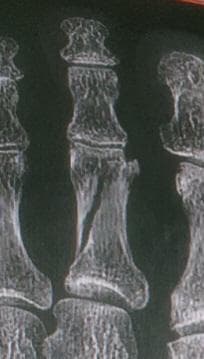

골절 사진 참부합니다. 이거 어긋난거 맞춰야되지 않나요?

저렇게 어긋나듯 삐져나왔는데요.

이거 좀.. 붙여서(?)?? 맞춰야되는거 아닌가요?

엑스레이상 뼈가 어긋나 보인다면 단순히 깁스만으로는 정렬이 안되고 변형이 남을 수 있습니다. 특히 골절이 삐져나온 듯 보이는 경우엔 정복 과정을 거쳐야 하는 상황일 수 있습니다.시간이 지나 뼈가 어긋난 채 붙으면 이후에 교정이 더 힘들고 변형이나 기능 저하가 남을 수 있습니다 가능하다면 빠르게 다시 확인 받아 정확한 정복이 필요한 상태인지 점검하는 것이 안전합니다!

우선 뼈 골절이 많이 어긋나는게 아닌 유합이 될 수 있다 판단하에 뼈를 정복 시키지 않은 것 같습니다.

뼈를 정복하는것도 여러 이유가 있어야 하지만 지금으로썬 엑스레이상 정복이 필요없다는 소견같습니다.